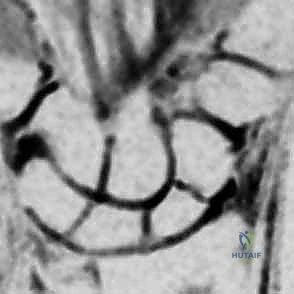

* التصوير بالرنين المغناطيسي (MRI): هو المعيار الذهبي لاكتشاف الكسور المخفية وتقييم التروية الدموية للقطب القريب.

* الأشعة المقطعية (CT Scan): تستخدم لتحديد شكل الكسر بدقة ثلاثية الأبعاد والتخطيط للعملية الجراحية.